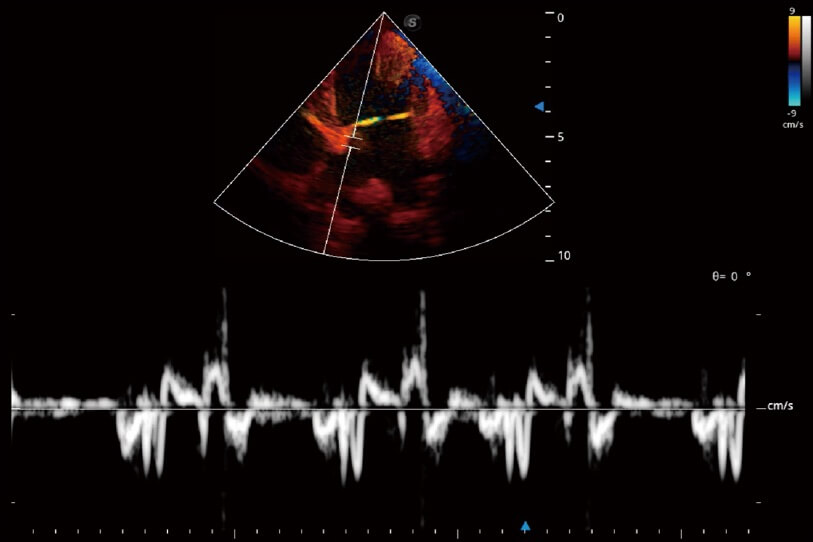

通過(guò)360度任意調(diào)節(jié)3條M型取樣線(xiàn),在同一心動(dòng)周期上觀(guān)察心臟不同位置的運(yùn)動(dòng)曲線(xiàn),得到準(zhǔn)確的心功能測(cè)量數(shù)據(jù),有效評(píng)估心肌運(yùn)動(dòng)及左心室功能。

實(shí)時(shí)用顏色表示心肌組織運(yùn)動(dòng),觀(guān)察和定量組織的運(yùn)動(dòng)情況,對(duì)快速檢測(cè)與評(píng)估心肌的灌注和活性、電傳導(dǎo)及心肌收縮和舒張功能等均能提供重要的診斷信息。

當(dāng)心臟測(cè)量結(jié)果超出正常范圍時(shí),可實(shí)時(shí)預(yù)警提示動(dòng)物醫(yī)生,減少疾病漏診概率。